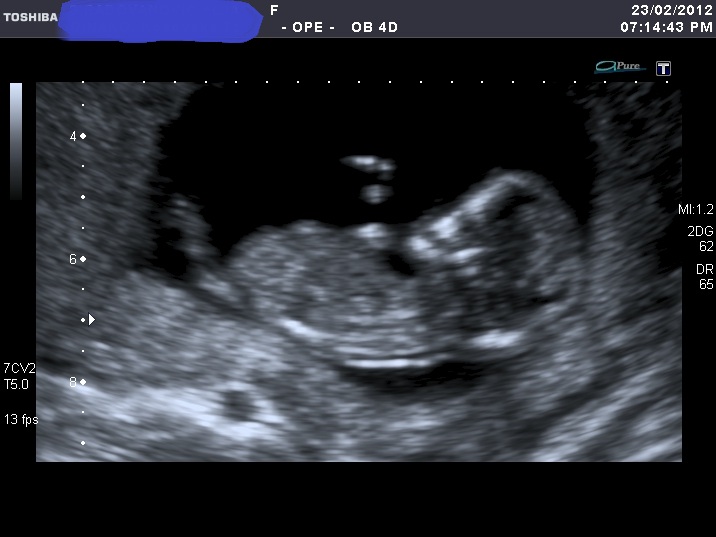

I'm sorry for spaming again with my nub shots, but now when I look at u/s pics I'm not sure I can a see a nub at all????

If you can see it, please enlighten me where to look. Also I think scull looks girly on some pics and boyish on the others.

I was 12 weeks, measuring 12 weeks 5 days